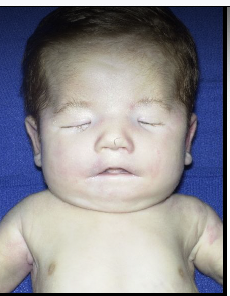

moebius sequence

paralysis of facial nerves, unable to form facial expressions

cloverleaf deformity

enlarged anterior fontanelle, other cranial sutures fused, hydrocephalus, macrocephaly